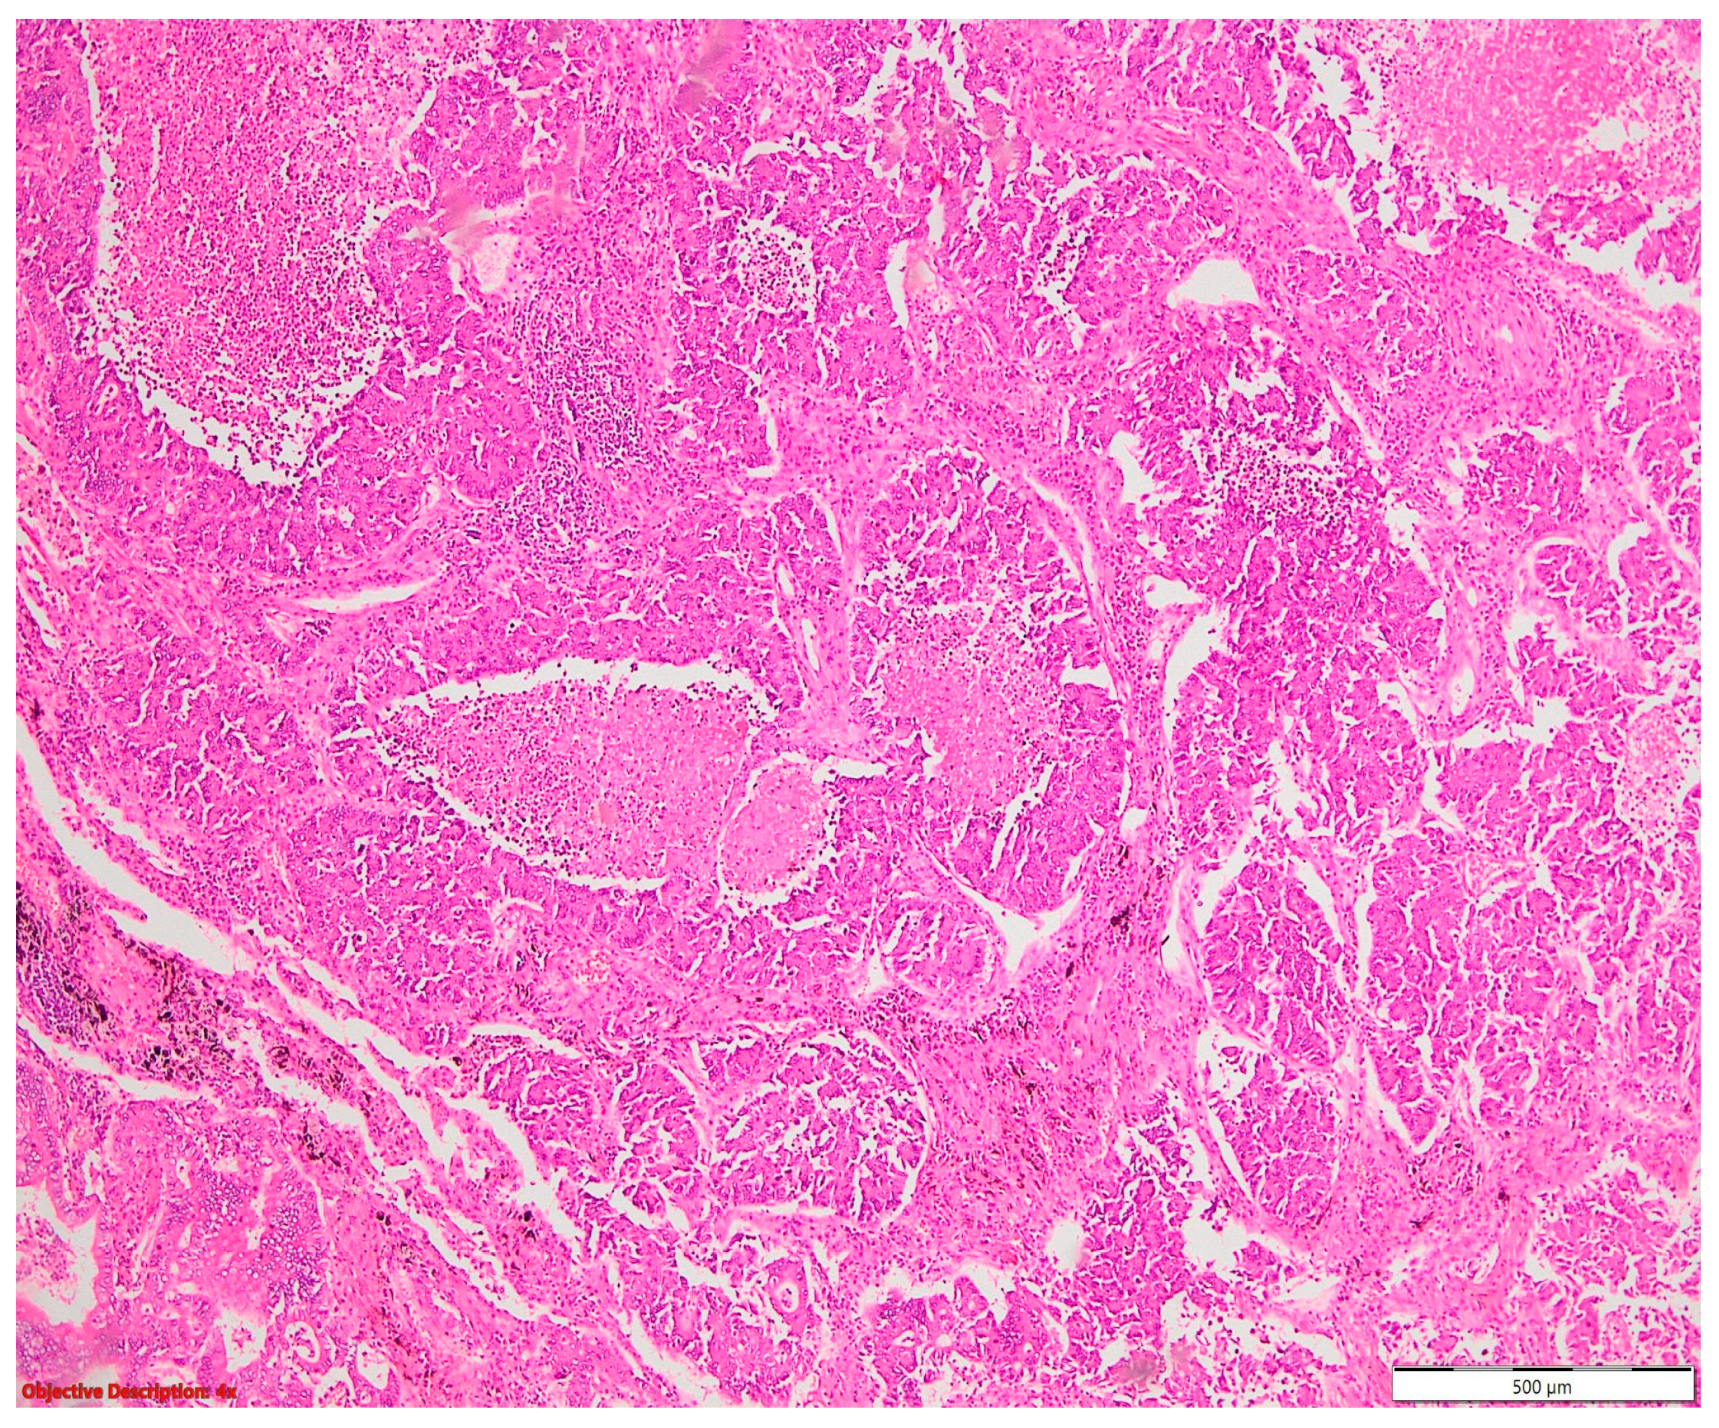

Tumorlets (Figure 14) were associated with adenocarcinoma in one case and another case with typical carcinoid (Figure 15) and sarcoidosis.

Figure 14.

Tumorlet—clusters of neuroendocrine cells (→) are present adjacent to a bronchiolar structure, with detached epithelium (→); significant inflammatory infiltrate; HE, 100×.

Figure 15.

Typical carcinoid: proliferation of neuroendocrine cells, without necrosis and/or mitotic activity; HE, 200×.

Women in their middle years, between 50 and 70, who have previously been diagnosed with cancer, particularly breast carcinoma, are more likely to develop tumorlets [33,34]. Even though they are surrounded by inflammatory and reactive tissue and fibrosis, tumorlets are typically asymptomatic and show no signs of severely restrictive or obstructive lung disease, even when they are numerous [33,34]. This highlights the indolent nature of tumorlets and underscores the importance of vigilant surveillance and management strategies, particularly in individuals with a history of cancer.